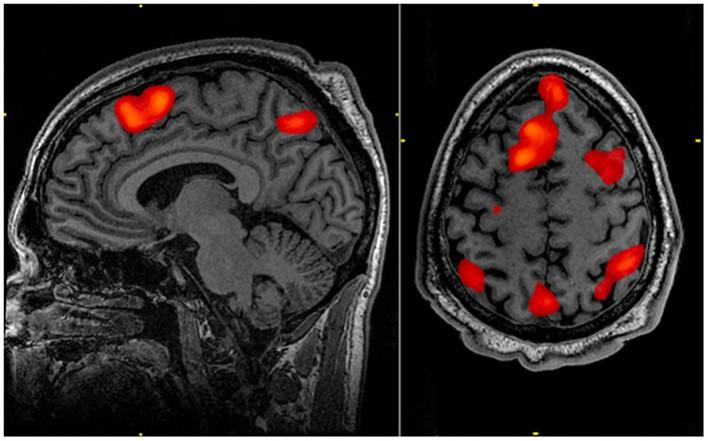

In a study conducted on mice, the scientists found pronounced effects of the soybean oil on the hypothalamus where a number of critical processes take place.

The research team discovered nearly 100 genes - including the 'love hormone' oxytocin produced in hypothalamus -- affected by the soybean oil diet.

"The hypothalamus regulates body weight via your metabolism, maintains body temperature, is critical for reproduction and physical growth as well as your response to stress," said Margarita Curras-Collazo, an associate professor of neuroscience and lead author on the study published in the journal Endocrinology.